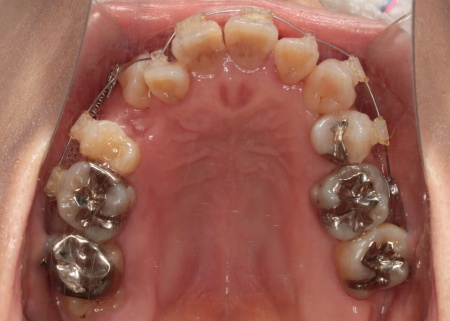

治療中

歯を移動させるスペースを確保する目的で、右上第1小臼歯、右下第2小臼歯、左下第2小臼歯の計3本と、温存が難しい右下第2大臼歯1本、合計4本の歯を抜きます。

温存が難しい右下奥歯を抜いたあとは、その後方にある親知らずを手前に移動させることで、機能面の改善と歯の寿命延長が期待できることを説明しました。

また、銀歯が装着されている歯を抜くことで下の歯がすべて白くなり、見た目の印象が改善されることも併せてお伝えしています。

また歯を効率よく動かすため、顎の骨に矯正用の小さなネジであるインプラントアンカーを埋め込み、それを固定源とすることでしっかりと歯を動かしながら、歯列と噛み合わせのバランスを整えています。